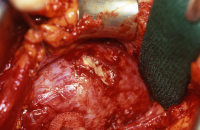

Die Nierenfreilegung und Abszessdrainage bzw. der postoperative Krankheitsverlauf im obigen Fall (s. Abbildung 6) sind in den Abbildungen dargestellt (Abbildung 9,10).